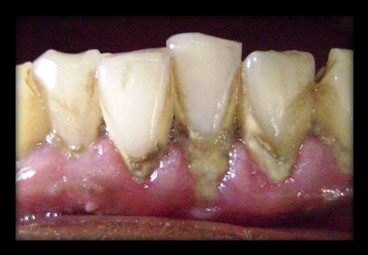

Gingival recession is the most common mucogingival deformity and should be treated at its earliest detection. Periodontal plastic surgery is a rapidly emerging field. A “laterally positioned flap”, has been used for root coverage in recession defect in mandibular anterior area, thereby allowing better esthetics, increase in attached gingiva, decreasing both hypersensitivity and cervical caries.

PRE - OP POST - OP